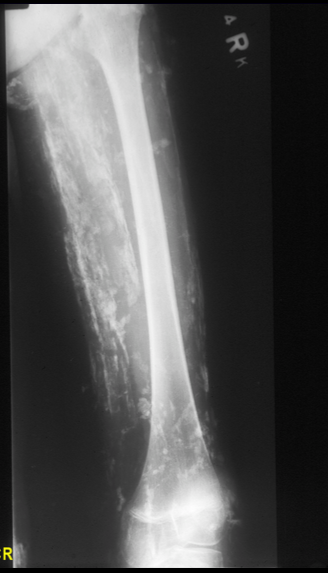

Wolff’s Law

force applied to bone surface –> bone deposition

force removed –> bone removed

woven bone in adult

pathological!!